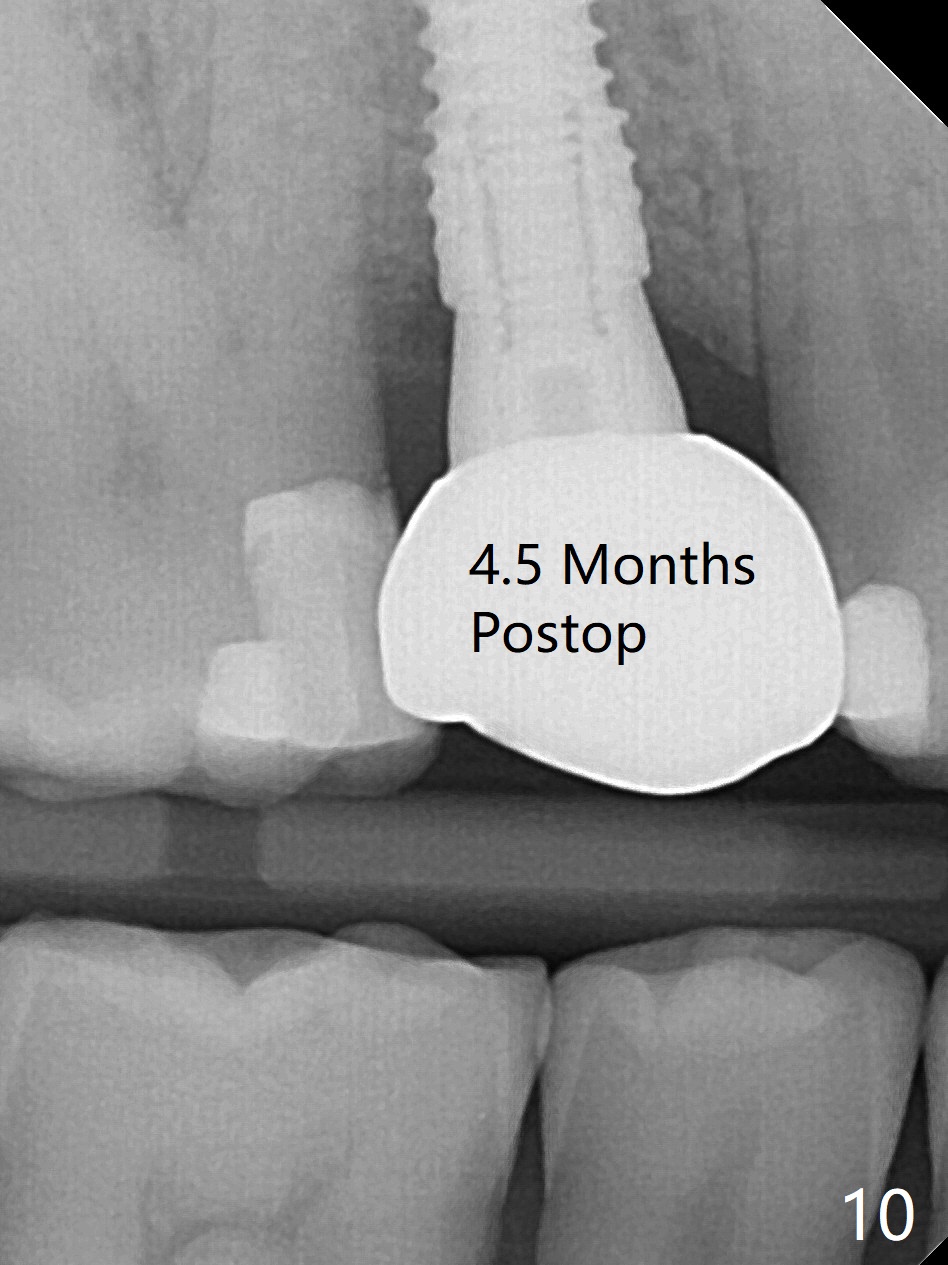

尽管没有任何症状,右上5牙冠粘固后2年5个月,牙冠与基台取出(没有使用扳手,说明基台未完全就位),切开,去除少量肉芽组织,仍然发现植体螺纹暴露(图一),使用一种叫I Brush 钛合金刷子清洁后,放置粘性骨块(图二: S),它坐在牙槽嵴上仿佛非常安稳,多么象马鞍(Saddle)。覆盖一张PRF膜和一小张Cytoplast(不可吸收膜,Osteogenics (company) 图三:箭头),使用PTFE缝线(与Cytoplast同样一种材料)缝合。术后即刻根尖片显示骨粉服服帖帖地坐落在植体和牙槽嵴上(图四:*)。最后覆盖牙周敷料。后者术后十天左右脱落,伤口愈合正常,颊侧瘘道仿佛消失,颊侧骨壁好像不再凹陷了(图五,六)。术后5周,膜已经脱落,缝线撤除后,伤口好像二期愈合,但愿肉芽组织下面骨粉尚未损失太多。术后三个月根尖片显示骨粉减少(图八)。不可吸收膜脱落可能造成骨粉流失。应该做减张缝合。术后4.5个月颊侧骨壁又凹陷(图九:箭头,需要decortication),但是uncover时植体周围都有骨质包绕,术后咬翼片也证明近中,远中骨质接触植体(图十:由于找不到合适愈合基台,直接放置基台和牙冠)。粘固后2.5个月虽然颊侧骨板凹陷,但是没有植体周围炎迹象(图十一)。